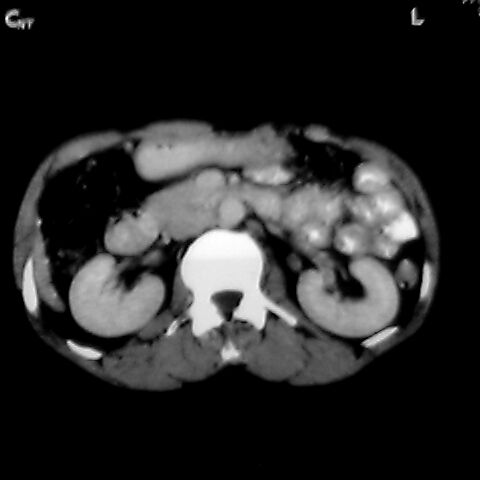

女 48岁 食道癌术前体检发现脾占位。

脾胀内部巨大低密度肿块,边界清或不清,中心坏死,轻度增强,内见散在钙化,结合食道癌病史多考虑:转移癌.

脾脏低密度灶伴钙化,增强化明显,中心见液化坏死灶,强化延时明显。考虑血管瘤。转移瘤待排。

考虑脾脏血管瘤,中央低密度为血栓形成